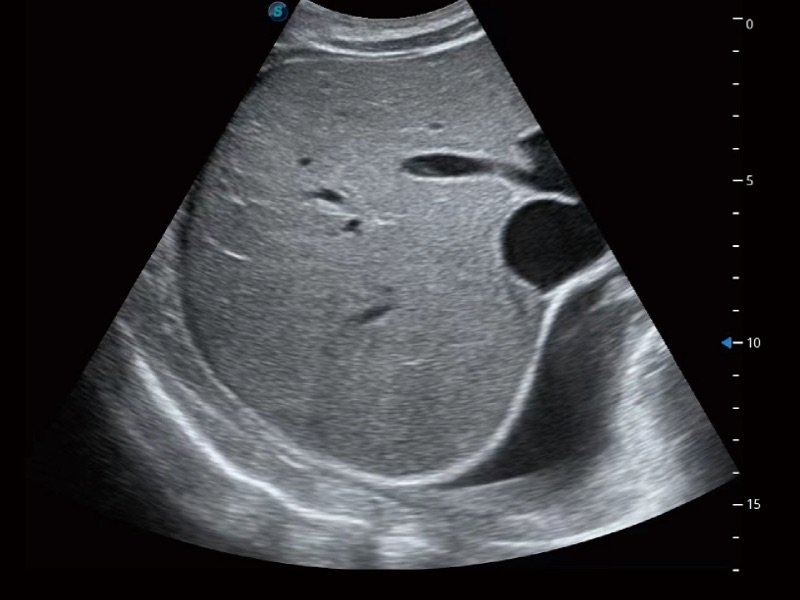

μ-Scan+

Die neue Generation der Bildgebungstechnologie μ-Scan+ bietet durch die Reduzierung des Rauschanteils, Steigerung der Bildqualität und verbesserte Kontinuität der Ränder eine bessere Bildqualität für naturgetreue Details und optimale Darstellung.